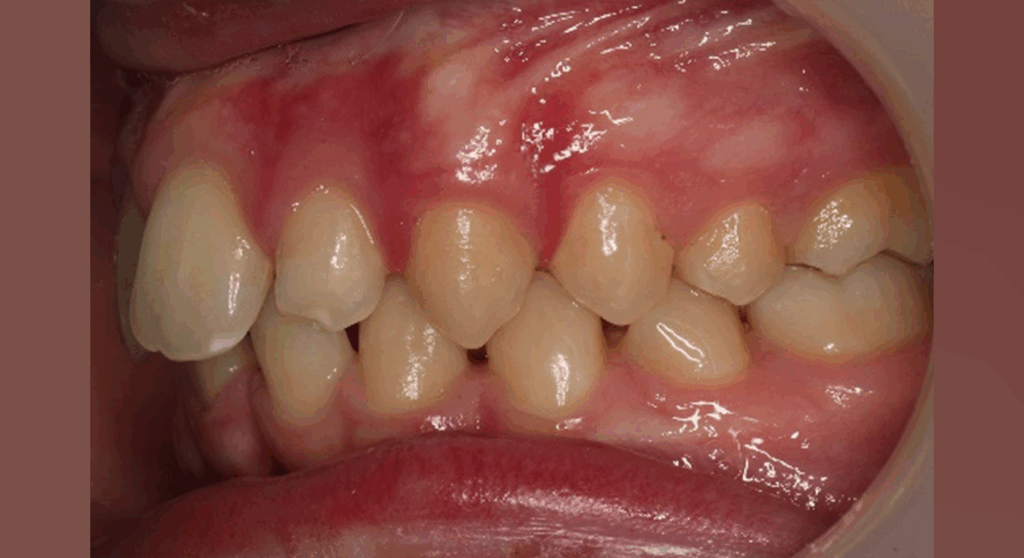

Skeletal Class II due to mandibular retrognathia, proclination of maxillary incisors, narrow arch creating a V-shaped arch, agenesis of 12, 31, 41, hyperdivergent facial pattern, moderate deep bite (2 mm), increased overjet (9 mm), asymmetric canine and molar Class II due to mandibular deviation to the left, maxillary midline deviation related to agenesis of 12, distal rotation of 35 and 45, and pronounced lower curve of Spee.

Upper arch: 20 active aligners

Transverse expansion

Derotation with mesial-out of first molars

Space opening for 12 by distalizing 13

Maxillary midline correction